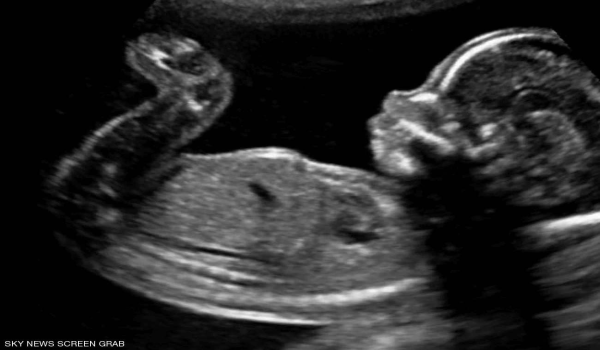

خمسة أشياء «غريبة» يقوم بها الجنين في رحم أمه

لا يتذكر الناس شيئًا عما فعلوه حين كانوا في أرحام أمهاتهم، لكن باحثين في الطب كشفوا عدة أمور يقوم بها أي جنين قبل قدومه إلى الحياة.

وبحسب موقع «ساينس فوكس»، فإن الجنين يقوم في بداية تشكله، بإحداث تغيير في الأوعية الدموية داخل الرحم لأجل إنشاء المشيمة التي تقوم بعملية حيوية خلال فترة الحمل.

وبفضل هذه المشيمة، يقوم جسم المرأة الحامل بنقل الغذاء والأوكسجين إلى الجنين داخل الرحم، وعلاوة على ذلك، ينقل الفضلات إلى الخارج، لكن التفاعل بين الأم والطفل لا يقف عند هذا الحد.

وكشفت الدراسات أن عددًا من خلايا الجنين تنتقل إلى الأم، وتكشف تحليلات الدم أن هذه الخلايا تبقى موجودة حتى بعد عقود من الحمل والإنجاب، وفي حالات أخرى، تنتقل خلايا جذعية من الجنين صوب قلب الأم ويكون لها دور إيجابي في تحسين النبض.

ومن الأمور التي قد لا نعرفها، هو أن الجنين يكون في بداية تكونه شبيهًا بسمك الجمبري إذ يبدو كما لو أنه ذو ذيل، لكن هذا يختفي مع مرور الوقت في الرحم، ولا يتبقى من هذا الذيل إلا عظم صغير نشعر به أحيانًا عند الجلوس.

وفي أمر ثالث، تأخذ أصابع الجنين شكلها الطبيعي بعدما كانت في هيئة مجاذيف، من خلال عملية تعرف بـ«انتحار الخلايا»، ويتم هذا التحول خلال الأسبوع الثامن من الحمل.

وبخلاف ما قد نعتقده، يقوم الجنين بإنتاج عدد كبير من الخلايا العصبية خلال فترة الحمل الأولى، وحين يضمن ربط الاتصال بين هذه الأعصاب وعدة مناطق من الجسم، تموت بعض الخلايا التي تدرك أنها لم تعد نافعة.